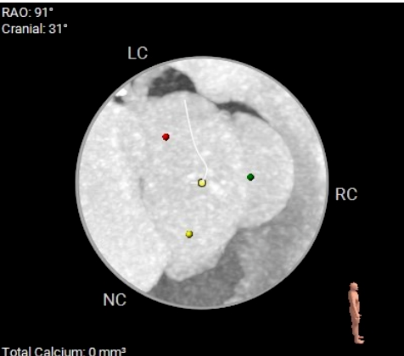

术前CT评估

Type I型三叶瓣,大瓣环,主动脉窦部扩张,近似横位心,双侧冠脉点状钙化。

(主动脉根部概览)

(主动脉瓣根部钙化概览)

双侧冠脉开口高度可,左侧瓣叶偏长,窦部空间可,无冠脉遮挡风险。